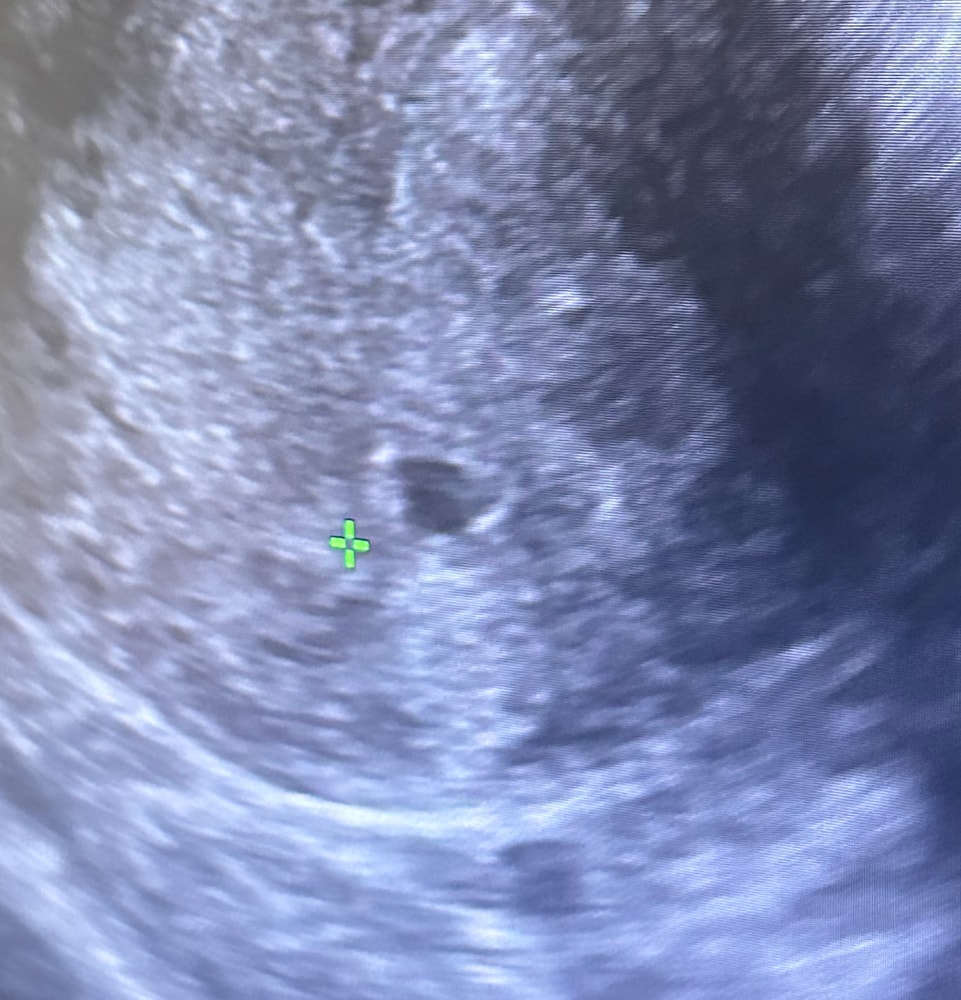

Viktoria, у меня 1,5 мм был Изображение

Viktoria, ну я видела у девочек разные плодные на фото Вроде у вас норм

Марии , там внутри будто бы что то есть , но врач ничего не сказала … Изображение

Viktoria, ну да что то есть Ещё бы понимать что и к чему 😅